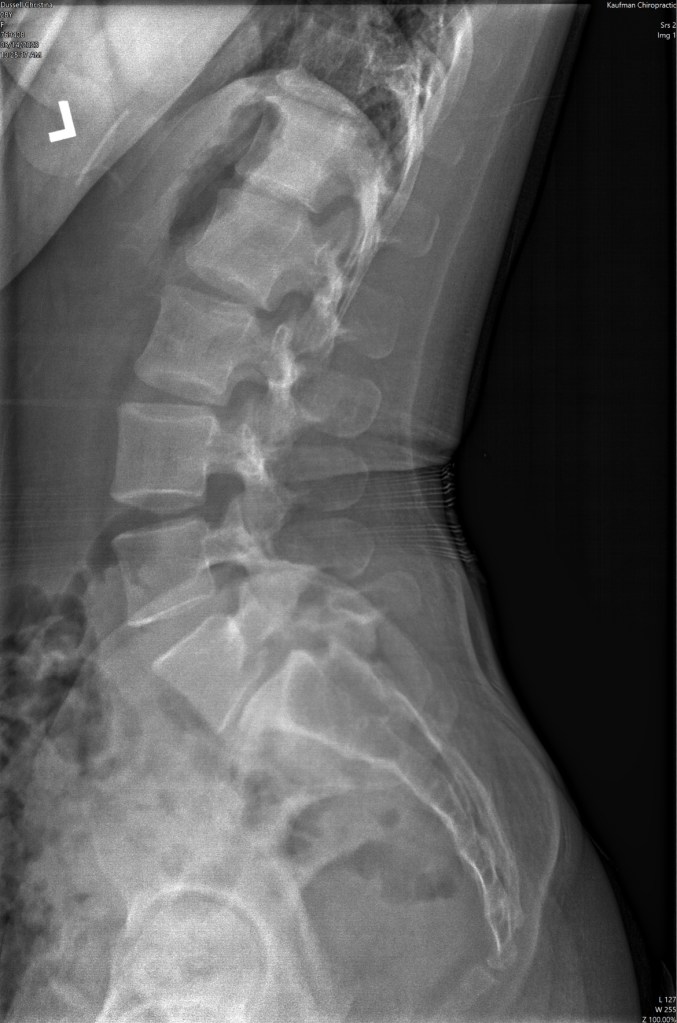

I also have chronic back pain that is related to a genetic issue that caused my L5 to break. Grade 2 isthmic spondylolisthesis, slight scoliosis, a thinning disc, and now sciatica. I feel like my mind and my spine are the crux that need to be managed so I can step forward instead of a feeling stuck in a stagnant state and feeling very limited.